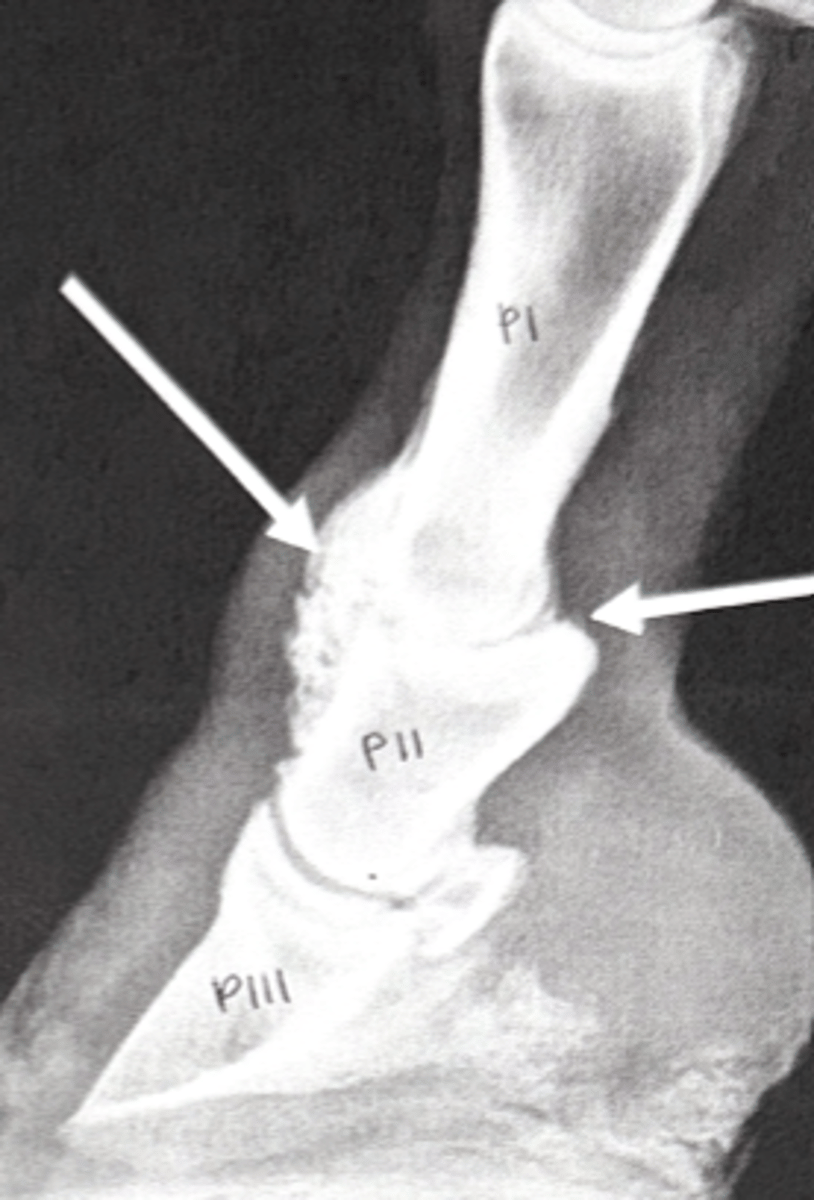

Collateral hoof cartilage

Which structure in this radiograph is ossified

Quittor

What is the layman's term for necrosis of this structure?

What synovial structures would be encountered by a puncture at A?

medial artery

What is the main arterial blood supply at the level of the carpus (travels through carpal canal)?

low ring bone

What is the layperson's term for osteoarthritis of the joint between the circles?

pastern joint

What is the layperson's term for the joint indicated by the arrows?

high ring bone

What is the term for osteoarthritis in this joint?